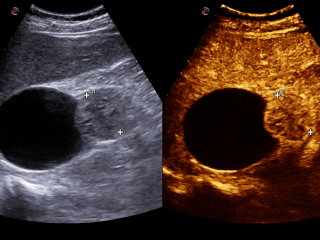

Die Ultraschalldiagnostik ist in allen Bereichen der Medizin eine der wesentlichen Säulen der bildgebenden Diagnostik und ist ein essentieller Bestandteil der täglichen Routine. Diese bildgebende Technik gehört zu der am schnellsten wachsenden Verfahren in der Medizin. Der medizinische Ultraschall, liefert in vielen Bereichen beeindruckende Fortschritte und führt zu einer Steigerung des aktuellen Wissens über moderne Diagnose- und Interventionstechniken. Für eine optimale Vorbereitung auf diesen Entwicklungstrends, Bedarfs es einer kontinuierlichen Aus- und Weiterbildung.